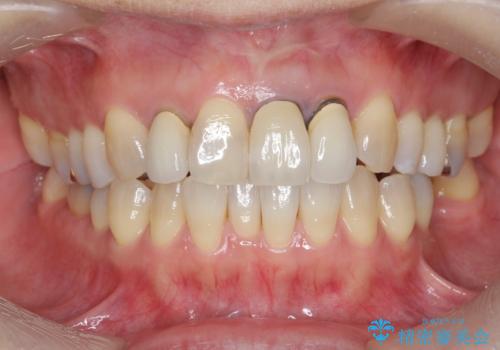

- 前歯のクラウンの歯肉の位置が年々変化し、歯ぐきのフチが黒くなってしまった、綺麗にしたいと希望されて来院されました。

装着されているセラミッククラウンを除去したのち、現在の歯ぐきのラインにしっかりと合う精度の高いオールセラミッククラウンを作製していきます。

- 39.6万円(ジルコニアクラウン×3・仮歯×3)費用は治療当時の料金となります

周囲の歯に調和したセラミッククラウンを作製し、審美性を大幅に向上させることができました。